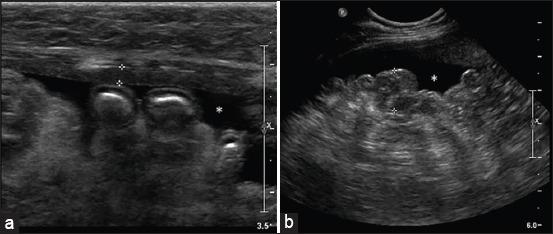

Feline infectious peritonitis (FIP) is an infectious disease characterized by non-specific laboratory changes and clinical signs. Clinical symptoms include anorexia, jaundice, fever, and weight loss. Moreover, some lesions are found in the digestive and respiratory systems. FIP, whose virulence varies, cannot be distinguished using several diagnostic methods. Moreover, feline coronaviruses (FCoVs) can be classified into two serotypes based on differences in their amino acid sequences, spike (S) protein sequences, and antibody (Ab) neutralization. There are two pathotypes, namely those caused by FCoV, which are often referred to as feline enteric coronavirus and FIP virus (FIPV). Furthermore, FIPV infection can be caused by sub-neutralizing levels of anti-FIPV S Abs. Therefore, a supporting diagnosis is needed to confirm FIP because there are no specific symptoms. This review aimed to provide updated information on FIP, including epizootiology, clinical and pathological characteristics, pathogenesis, hematology, clinicopathological and imaging features, pathological features, experimental infection, treatment and prevention, infection and immunity, animal and public health considerations.

猫传染性腹膜炎(FIP)是一种以非特异性实验室变化和临床症状为特征的传染病。临床症状包括厌食、黄疸、发热和体重减轻。此外,在消化系统和呼吸系统中发现了一些病变。FIP的毒力各不相同,无法通过几种诊断方法进行区分。此外,猫冠状病毒(FCoV)可根据其氨基酸序列、刺突(S)蛋白序列和抗体(Ab)中和作用的差异分为两种血清型。有两种致病型,即由FCoV引起的,通常称为猫肠道冠状病毒和FIP病毒(FIPV)。此外,FIPV感染可能由抗FIPV S抗体的亚中和水平引起。因此,由于没有特异性症状,需要进行辅助诊断来确诊FIP。本综述旨在提供有关FIP的最新信息,包括流行病学、临床和病理特征、发病机制、血液学、临床病理和影像学特征、病理特征、实验感染、治疗和预防、感染和免疫、动物和公共卫生考虑因素。